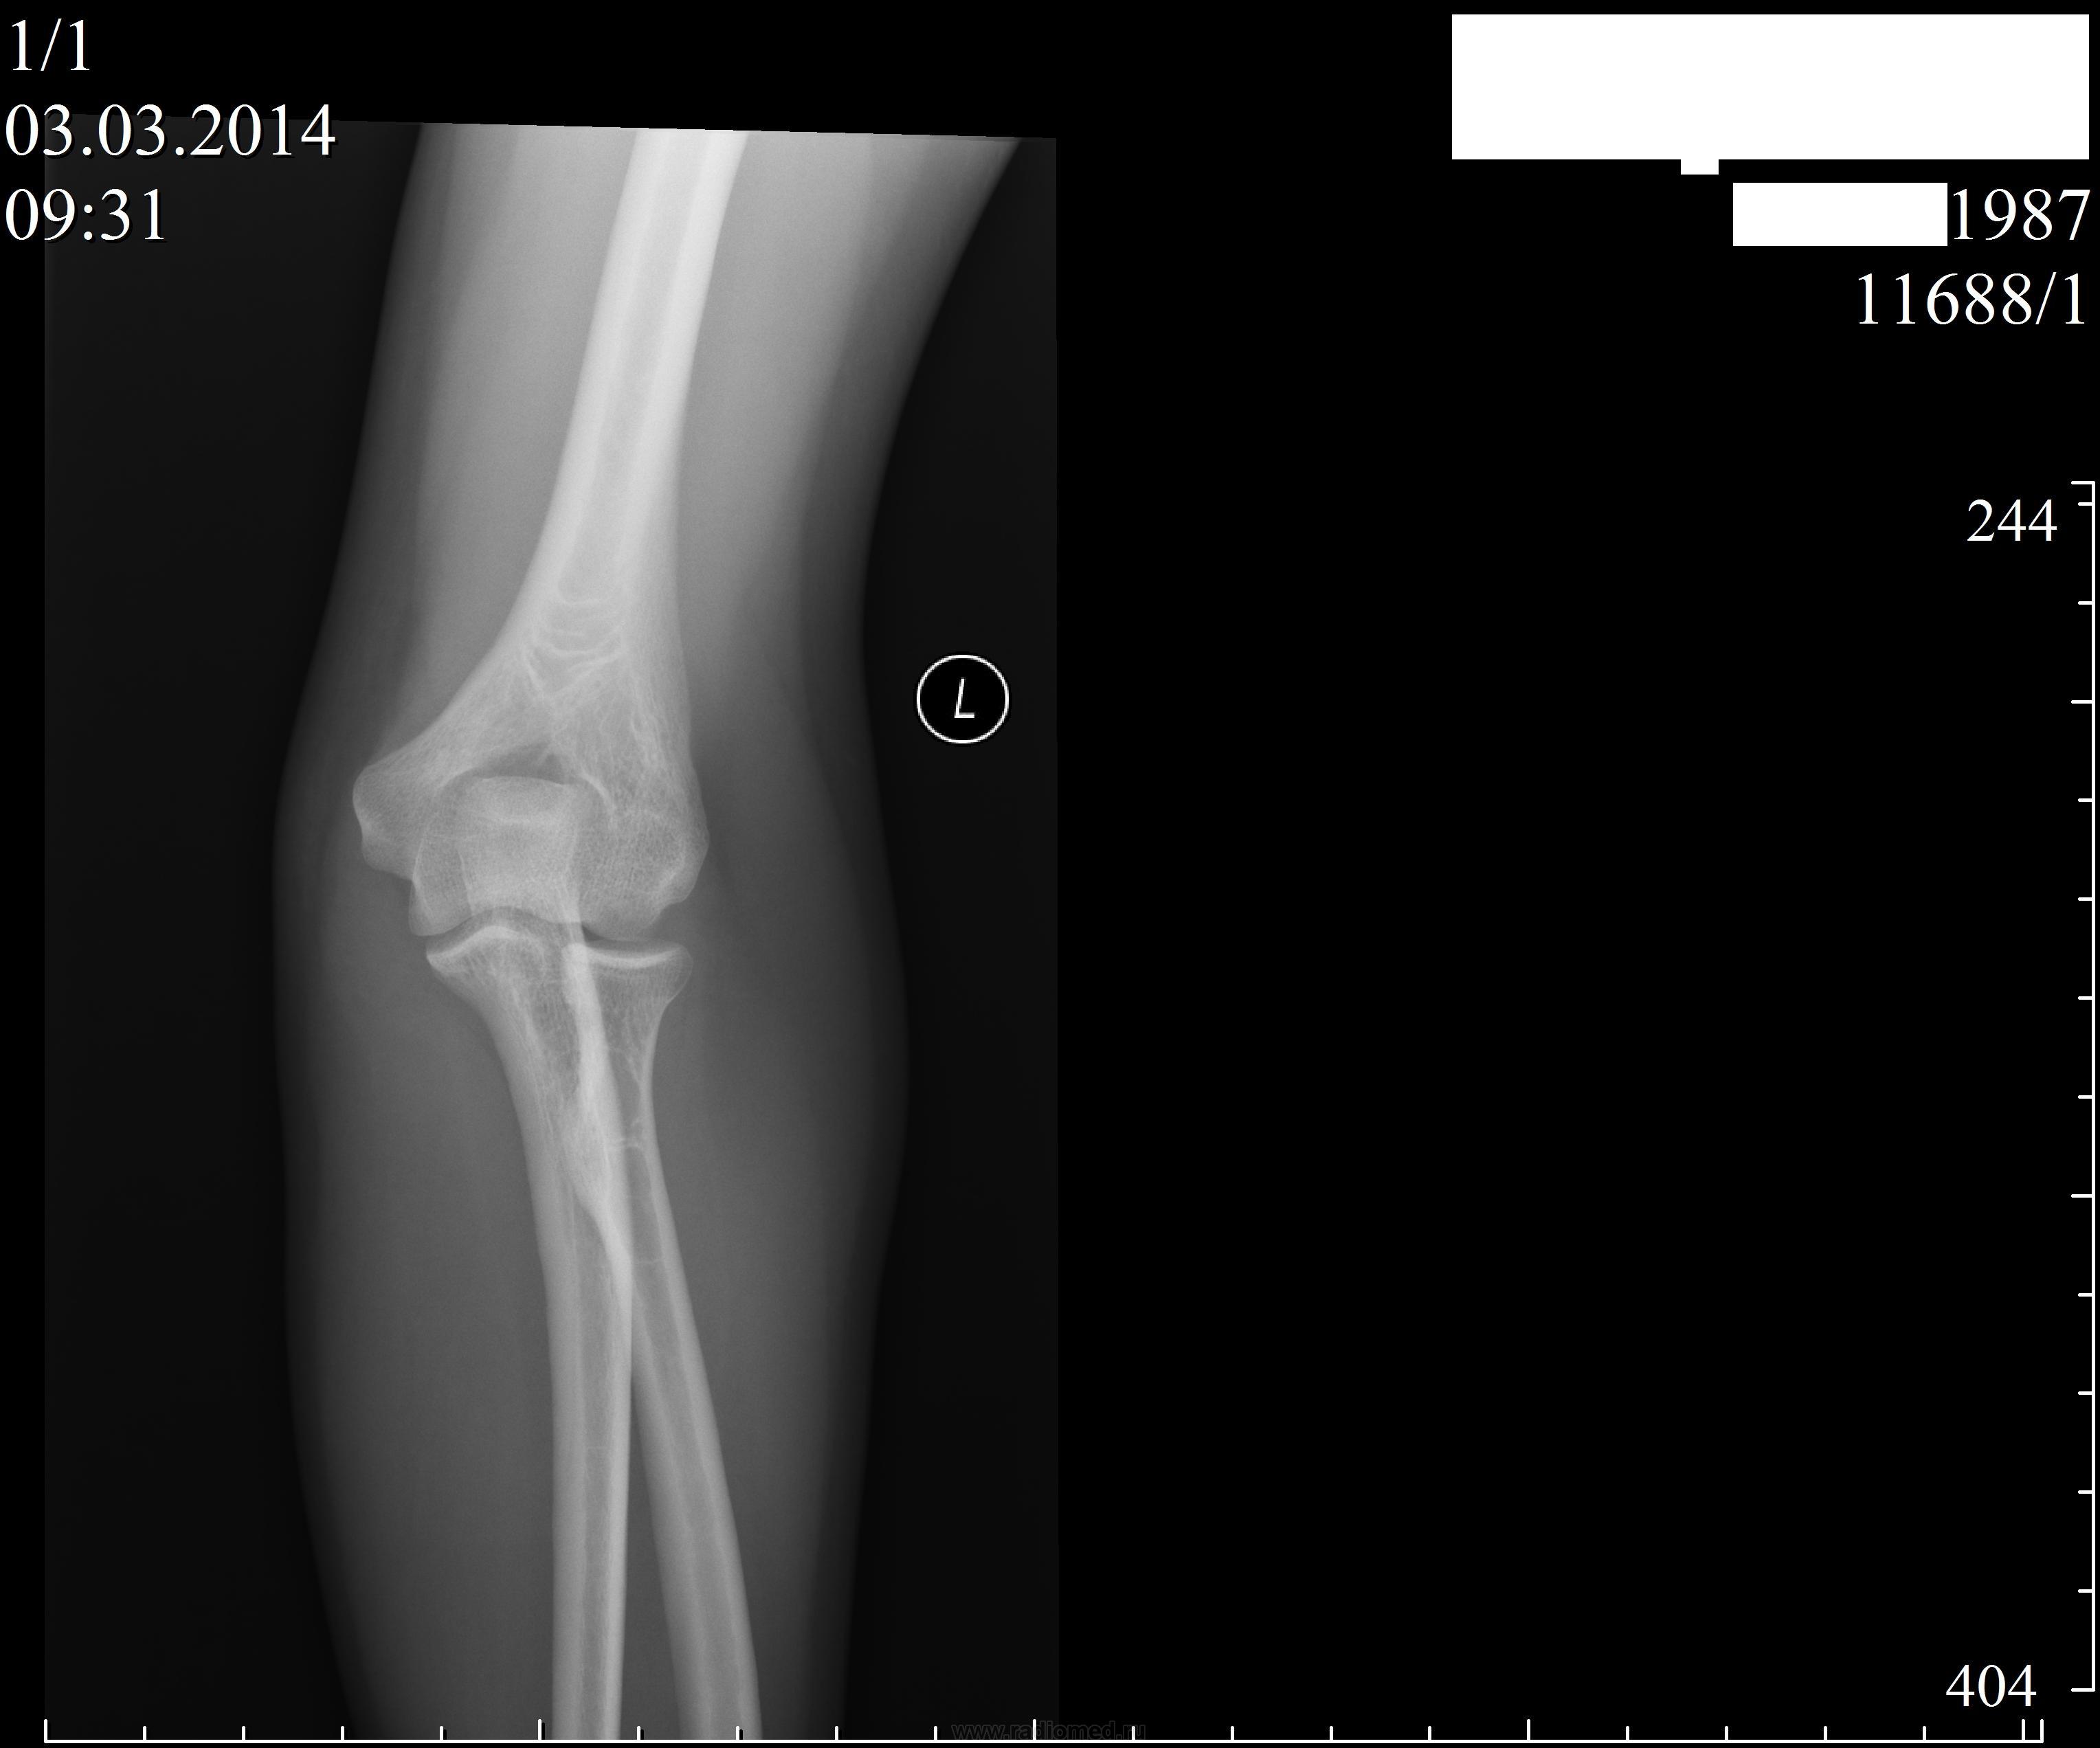

Пациент 26 лет.Направлен хирургом.DS. бурсит левого локтевого сустава.

Возникли вопросы по оценке структуры проксимального метадиафиза лучевой кости.Можно ли это расценивать как вариант нормы? Если патология, то какая? Вопрос №2:если на R-грамме признаки бурсита?

Я тоже такую структуру, как в лучевой кости не считаю патологической. В локтевом отростке обратила внимание на небольшой очаг просветления. Признаков бурсита не вижу (как косвенные расценила бы утолщение и уплотнение периартикулярных тканей.На представлееных Вами снимках мягкие выглядят обычно.) Качество снимков вызывает зависть (по - хрошему).

Это бугристость луча - место прикрепления бицепса. А диагностировать бурсит по рентгенограмме не очень уместно...

Уважаемый коллега! Ну ведь не просто так снимки положены. Конечно, есть перестройка структуры луча в виде кистоподобных просветлений + в локтевой кистоподобная тень. Что это- анатом расскажет. Т.е. описать можно, субстрат неизвестен, на скорость жизни вроде не повлияет. Но описать надо бы. Всяк бывает потом.

+1.Есть вкрапления извести-субклинические энхондромы??-находки.